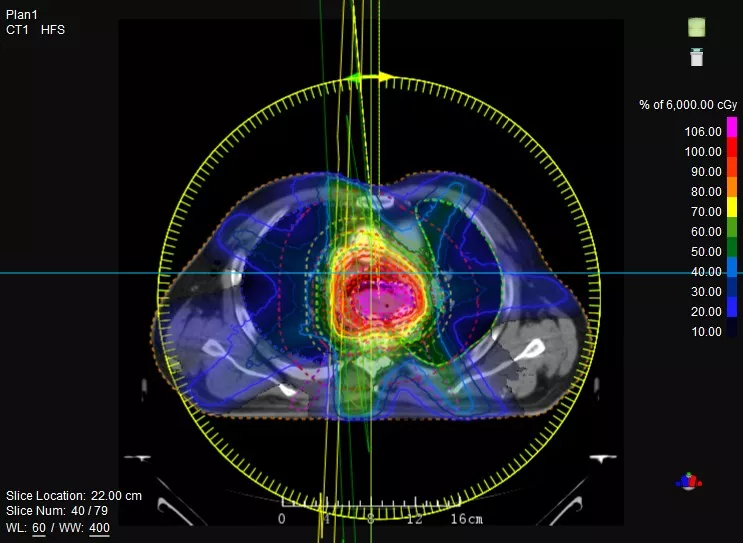

機載CT影像可直接用于放療計劃制作

CT-IGRT配準,除骨性標記外,還能以器官、軟組織等作為參考,真正找到配準目標

一體化CT-linac讓自適應(yīng)放療ART概念變?yōu)楝F(xiàn)實?;颊呷煶虪顟B(tài)監(jiān)控,適時在線調(diào)整治療計劃,精準控制治療劑量,為患者動態(tài)定制個體化治療方案。uAI賦能智能勾畫和自動計劃,秒級勾勒靶區(qū)和危及器官,大幅縮短自適應(yīng)放療時間。

聯(lián)影CT-linac全程監(jiān)測治療過程病灶的變化,及時調(diào)整和優(yōu)化治療方案